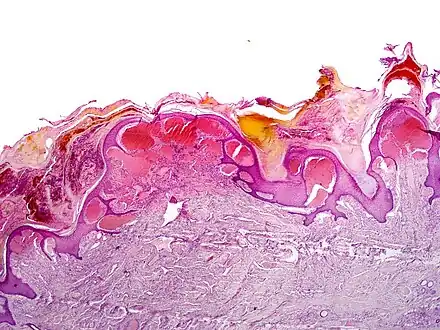

Angiokeratomas characteristically have large dilated blood vessels in the superficial dermis and hyperkeratosis (overlying the dilated vessels).

Scrotal angiokeratoma (Mibelli type); blood vessels close to the epidermis